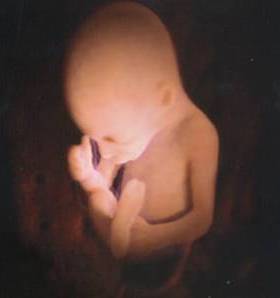

Il bambino ora prende quasi 200 grammi a settimana, pesa circa 1250 grammi e i suoi polmoni continuano ad esercitarsi nella respirazione. La testa cresce per fare spazio al cervello che ogni giorno vede nascere miliardi di nuovi neuroni, scalcia a più non posso ed è possibile contare i suoi movimenti per verificare il suo benessere e controllare che sia ben ossigenato. Per farlo, mettiti sdraiata su un fianco ogni giorno alla stessa ora, rilassati e concentrati su di lui, poi conta quanto tempo occorre al tuo piccolo per farsi sentire almeno dieci volte, conterai calci, pugni, singhiozzi e anche movimenti della testa e del sederino. La buona regola è che non servano più di due ore per arrivare a dieci.

Il bambino continua a crescere e ormai occupa quasi interamente lo spazio nell’utero.È possibile avvertire movimenti netti e precisi, al punto che potresti distinguere bene di quale parte del corpo si tratta, se la testa, il sederino o anche la schiena.

Il bambino è arrivato a circa 1400 grammi, è più cicciottello e la sua pelle è più liscia e rosea.Con le sue continue capriole, potrebbe trovare la posizione definitiva per la nascita.

Ora il piccolo pesa circa 1600 grammi, ogni giorno che passa mette su il grasso sottocutaneo e la pelle è meno rugosa, lo spazio disponibile è poco e i suoi movimenti sono meno “tellurici”.

L’utero è arrivato a circa 12 centimetri sopra la linea ombelicale trasversa e il piccolo pesa circa 1800 grammi ed è lungo circa 40 centimetri.

La peluria che lo ricopre comincia a scomparire mentre la vernice caseosa lo ricopre totalmente. Gli occhi distinguono la luce dal buio e, soprattutto, distingue il caldo dal freddo, al punto tale che si muove se viene posta una fonte di calore vicino alla pancia.